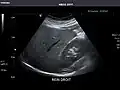

Kidneys: Right and left kidneys measure 11.5 cm and 12 cm in length respectively. No hydronephrosis. Small left lower pole kidney cyst.

Left kidney -